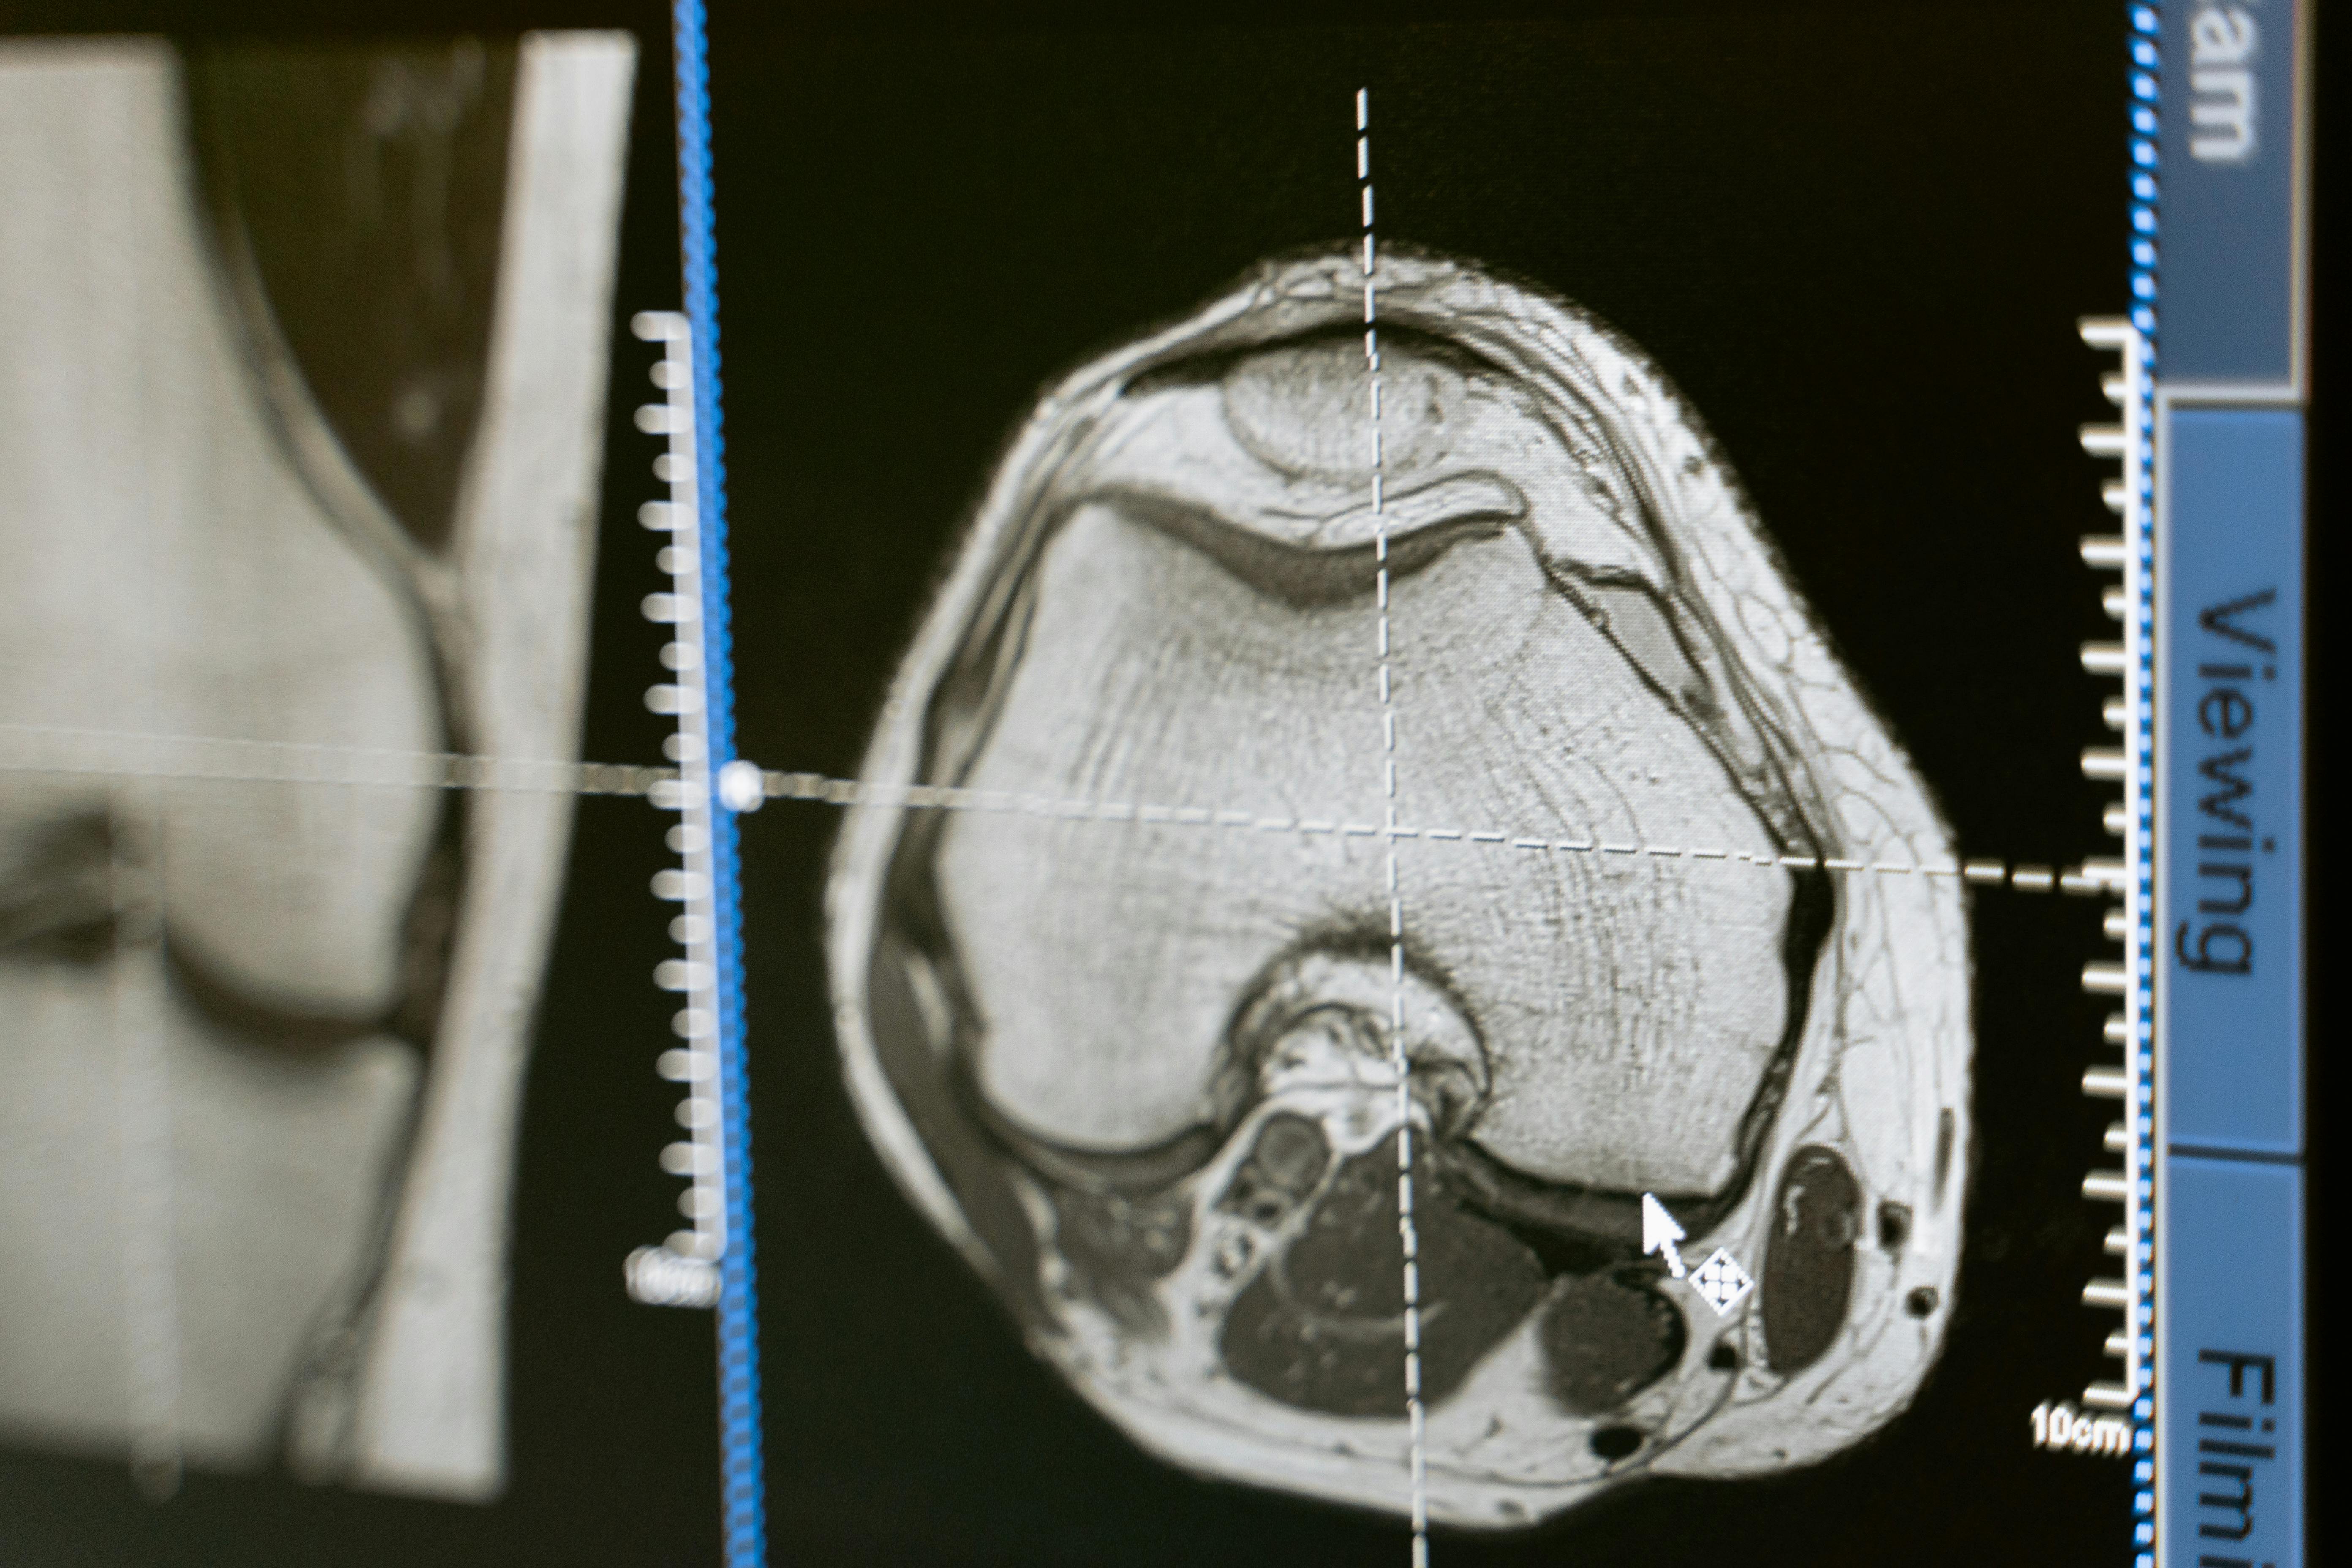

| 뇌 MRA | 뇌동맥류, 뇌출혈 위험 확인 가능 |

- 무증상자 허리/무릎 MRI: 의미 없음